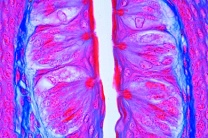

Künstliches Homo-Skelett, Naturabguß eines männliche Erwachsenenskelettes